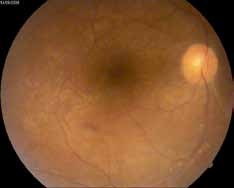

Vascularites rétiniennes

La vascularite rétinienne est fréquente. Elle peut être veineuse le plus souvent, mais aussi artérielle et se traduit par des lésions de périphlébites, de périartérites et de thromboses vasculaires (5).

On observe le plus souvent une périphlébite occlusive, caractérisée par un engainement de la paroi veineuse réalisant un aspect de « brume » floconneuse blanchâtre entourant la colonne sanguine. L’atteinte est segmentaire (figure 3).

L’angiographie à la fluorescéine est un examen capital car elle permet de faire le bilan de l’atteinte rétinienne, et de retrouver des anomalies infra cliniques dans 6% des cas à type de vascularites rétiniennes (figure 4).